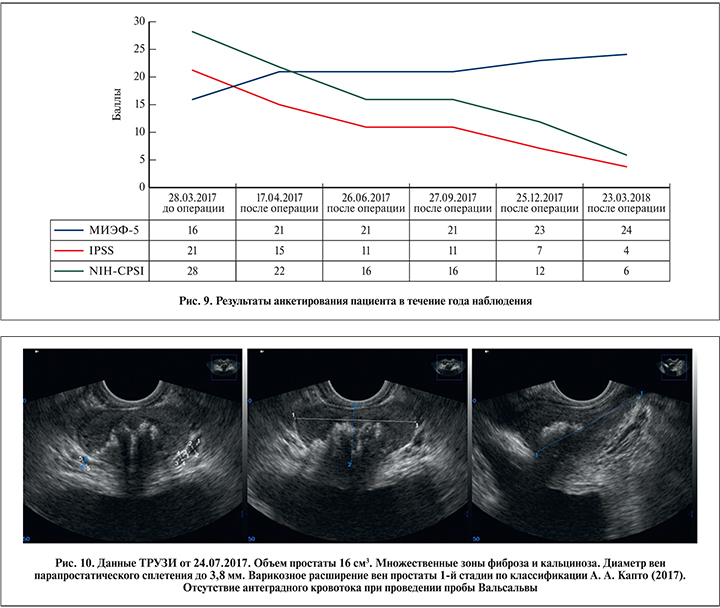

Жалобы оценивали при помощи вопросников МИЭФ-5, IPSS, NIH-CPSI, оценки по которым составили 16, 21 и 28 баллов соответственно.

Послеоперационное ведение включило: 1) антикоагулянтную терапию – ривароксабан 20 мг в сут. в течение 6 мес. после операции; 2) ультразвуковое ангиосканирование подвздошных сосудов в 1-е сутки, через 2 нед. и через 1, 3, 6 мес. после операции. Результаты оперативного лечения оценивали при помощи вопросников МИЭФ-5, IPSS, NIH-CPSI, а также на основании данных ТРУЗИ (до операции и через 1, 3, 6 и 9 мес. после операции) (рис. 9).

В ближайшем послеоперационном периоде (в течение 1 ч) жалобы на боли в области малого таза практически исчезли, а через 1 нед. после операции пациент отметил восстановление эрекции без проведения какой-либо терапии.

Через 3 мес. после ангиопластики и стентирования отмечено уменьшение максимального диаметра вен предстательной железы на 45%, по данным ТРУЗИ, и отсутствие антеградного кровотока при проведении цветного допплеровского ТРУЗИ простаты в покое и при пробе Вальсальвы (рис. 10). Результат сохранялся на протяжении 12 мес. наблюдения. В целом отмечено уменьшение венозного полнокровия простаты, которое сопровождалось уменьшением болевого синдрома и восстановлением половой функции. Причем данный результат, сохранявшийся в течение всего периода наблюдения, достигнут без проведения терапии болевого синдрома, хронического простатита и эректильной дисфункции. Через 6 мес. после операции отмечена редукция варикозно расширенных вен яичек и их придатков. По данным УЗИ органов мошонки, диаметр вен гроздевидных сплетений в клиностазе в спокойном состоянии был менее 2 мм. Рефлюкс отсутствовал как в клино-, так и в ортостазе при пробе Вальсальвы.